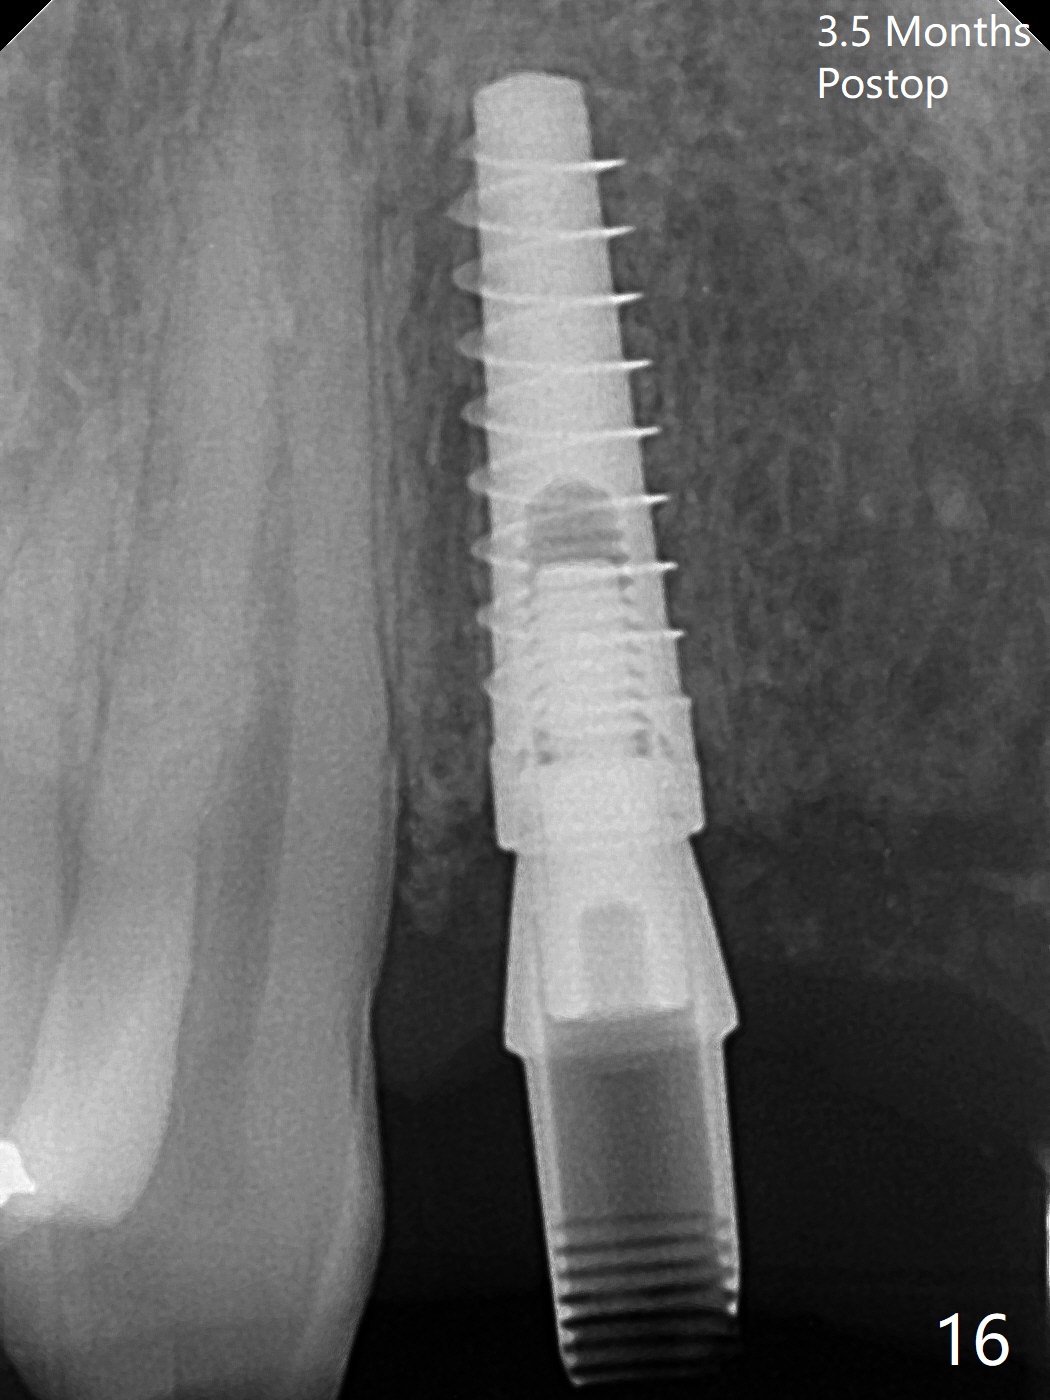

拆除部分桥发现:中,侧切牙牙龈红肿(图一),不利于切口和伤口愈合。不过还是在中切牙区切开,牙龈相当厚,有利于今后牙龈形成凹陷和乳头。坏消息是近远中距离太短,不利于植牙以及今后局部卫生维护,所以决定只在侧切牙种植(图二,三),完成钻洞后,颊侧根尖穿孔植骨,然后植入植体,即刻放置修复基台(图四 (*:牙龈乳头)),暴露基台牙龈缘,制作临时悬臂桥 (图五),两个中切牙牙冠长度差不多,插入临时桥时颊侧牙龈乳头基本形成(图六:*),缝合前颊侧,腭侧牙龈瓣下放置粘性骨块(图七,八:* )和PRF膜(图七:^)。最后使用牙周敷料。但愿术后牙龈炎症消失,形成良好牙龈乳头和pontic concavity。 其实由于口腔卫生习惯,术后十七天颊侧牙龈仍红肿(图九),而腭侧正常。如果口腔卫生改善而红肿依然存在,让实验室制作临时桥。术后一个月颊侧牙龈红肿好些(图十),好像骨粉丢失少许,可能与水枪使用有关。右上1牙冠显得太短(*)。也太肥大,因为右上1切缘太颊侧,与左上1对比(图十一:*)。由于颊侧牙龈(图十二:B)术中推向颊侧,与腭侧(P)牙龈之间放置大量粘性骨粉,术后一个月骨粉(<)形成牙龈,形成凹陷。颊侧萎缩不再明显了。右上1牙冠颈部多加些树脂,牙齿就显得长的多(图十三:箭头)。与侧切牙之间颈部故意留下间隙(*),让牙龈入位(空箭头),形成龈乳头。当右上1临时牙冠切缘(图十四:*)移到腭侧,外形改观不少。下次改善侧切牙唇侧。术后两个月三个星期牙龈红肿好像减轻,牙龈没有进入切牙间隙,干脆用树脂关闭(图十五:> <)。下次减少侧切牙切缘(^),适当增加中切牙长度(上提牙龈)。术后3.5个月植体好像整合,基台完全就位(图十六)。术后3.5个月Pontic凹陷形成,但是1,2之间龈乳头始终无法形成(图十七)。以后类似病例应该多种植一个。此例草率取模,可能需要临时粘固,观察植体近中颊侧所谓瘘道,必要刮治。由于比色不佳,需要实验室颜色更改,病人强化卫生,术后七个月,永久性牙冠粘固前,局部牙龈健康(图十八)。